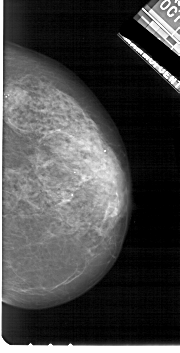

A_1722_1.RIGHT_CC

RIGHT_CC LINES 5281 PIXELS_PER_LINE 2686 BITS_PER_PIXEL 12 RESOLUTION 43.5 NON_OVERLAY